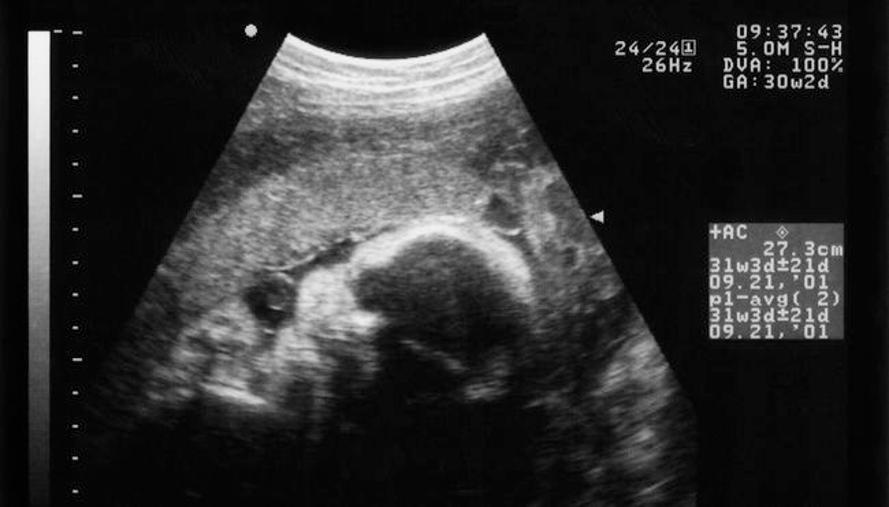

의사협회는 2009년 1월부터 2012년 5월까지 GE헬스케어에 대해 한의사에게 초음파진단기기를 거래하지 말라고 요구하고, 실제 거래 여부를 감시했다.

이에 대해 공정거래위원회는 "보건복지부 유권해석에 따르면 의료법상 한의사가 초음파기기를 구입하는 것은 불법이 아니며, 학술, 임상 연구를 목적으로 일반 한의원에서 사용이 가능하다"고 지적했다.

2007~2009년까지 GE와 삼성메디슨이 한의사에게 초음파기기를 판매한 것은 각각 10대씩이었다.

하지만 의사단체들이 위와 같은 압박을 한 이후 현재까지 한의사에게 판매한 실적이 전무한 것으로 나타났다.